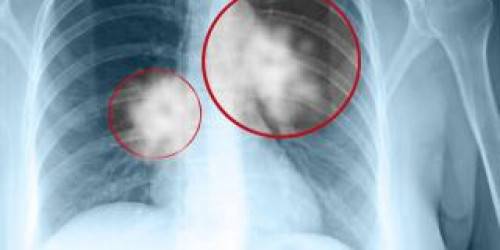

Ето как да разпознаем рака на белия дроб

Шансът за оцеляване се увеличава, ако ракът на белия дроб се диагностицира на ранен етап.

Затова лекарите обясниха няколко начина, чрез които може да установите тази болест.